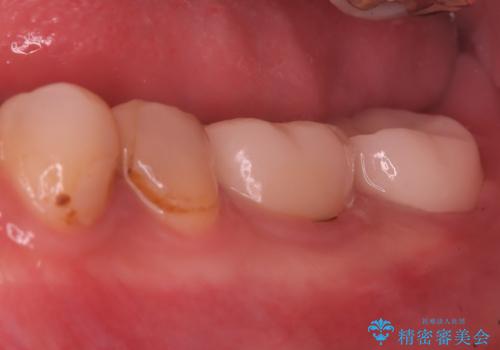

- 左下の奥歯の治療の継続を主訴に来院されました。

1週間ほど前に、自発痛の既往があり他院で応急処置を行ってもらったとのことです。

根尖部に透過像を認め、①何もしないと今後の経過として痛みが増悪することや、腫脹を伴うことがある。

病気の原因は細菌であるため、細菌数を減らすための処置として一般的に②根管治療という選択肢がある。再根管治療の場合は病気が治るのは7割ぐらいであり、それでも治らない場合は意図的再植術を行い9割近くまで成功率を高めることができる。ただし、今回のケースでは根尖が湾曲しているため意図的再植時の破折リスクが高いため適応は難しい。また、根尖の病変が治ったとしても、歯周病、カリエス、脱離や破折リスクがあり治療後抜歯になる可能性もある。治らない可能性や治療したとしても抜歯になる可能性があることを考慮し、③抜歯の選択肢をとる場合もある。